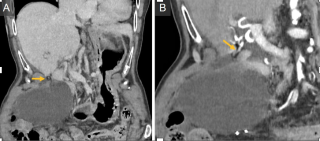

Case presentation

A 65-year-old woman with rectal adenocarcinoma (pT4bN0R2, KRAS-mutated) treated with neoadjuvant chemoradiotherapy, and extensive pelvic surgery developed chronic right-sided ureteral obstruction requiring long-term ureteral stenting. From 2023 onward, she experienced recurrent episodes of pyelonephritis, with urine cultures repeatedly isolating enteric organisms. In 2025, pelvic magnetic resonance imaging and retrograde ureteropyelography revealed right-sided hydronephrosis and a fistulous tract connecting the distal right ureter and the rectosigmoid colon, without evidence of tumor recurrence. Surgical management consisted of a bloc resection of the fistula, proctectomy with perineal closure, right ureteral reimplantation, terminal colostomy, and omentoplasty. The postoperative course was uneventful.